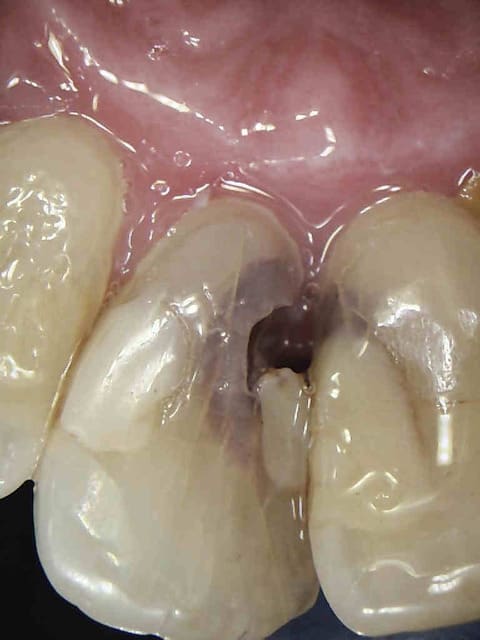

chicot29

> Honnêtement, la dent est quand même bien niquée !

> Fêlure mesiale et distale, le curetage n'est pas complet sur l'arrête restante.

Pour en revenir au cas de départ présenté par Chicot29, sauf pathologie pulpaire, cette dent à simplement besoin d'une bonne couronne. L'histoire de la dévitalisation c'est dans nos têtes de dentistes que ça se passe, et l'IC j'en parle même pas parceque je serai grossier.

Je fais aussi souvent des couronnes sur dents vivantes . Par contre dans le cas present , j'y reflechirai à deux fois : grosse obturation, nombreuses felures (atteinte pulpaire ?) et retraction pulpaire +++ .